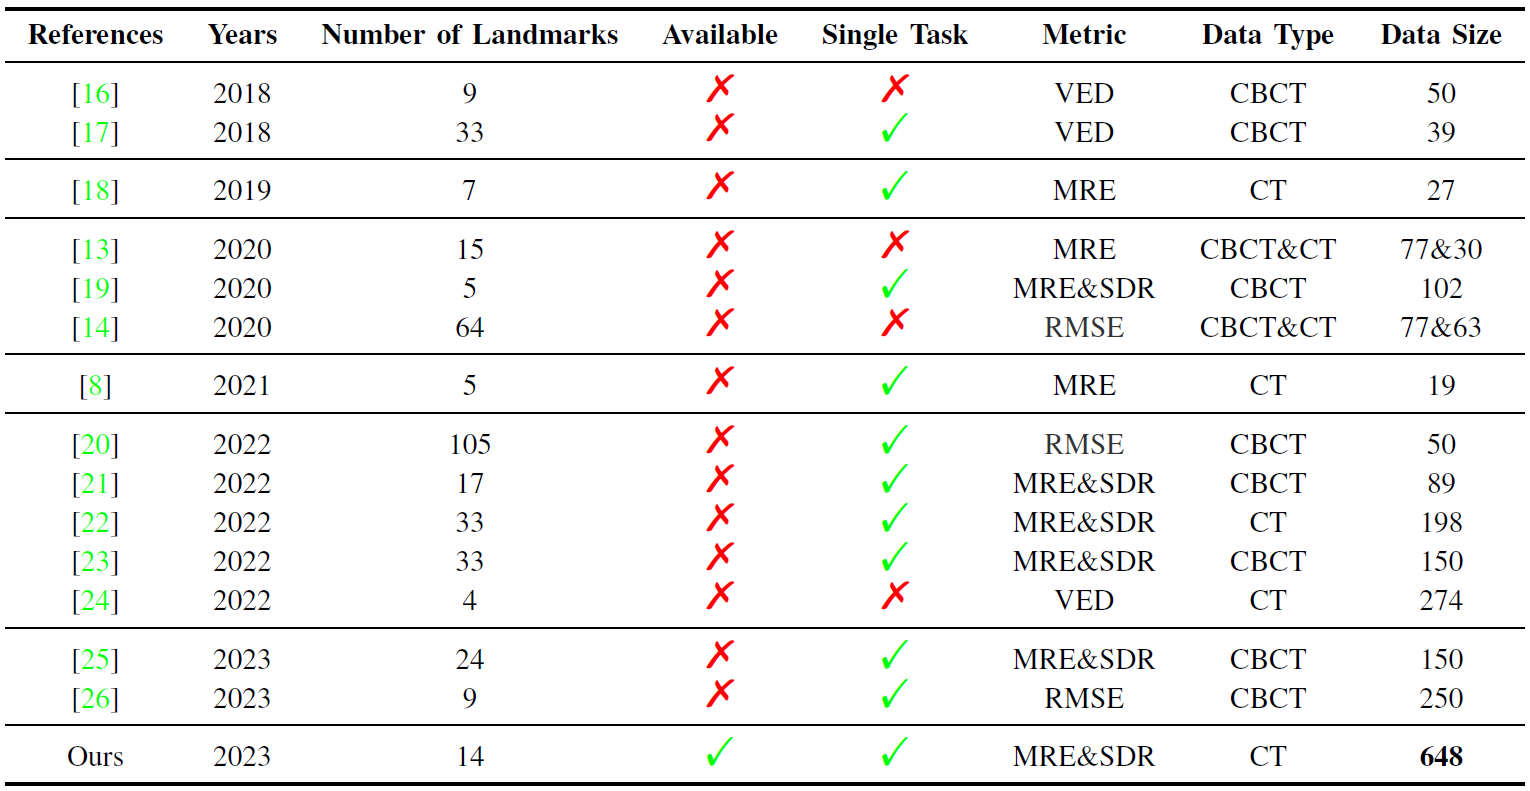

- The lack of a standard benchmark dataset to evaluate the performance of automatic landmark detection models is a significant constraint. Through a review of advanced models from 2018 to 2023, listed in the Table, it was found that these models were trained on private datasets with variable data sizes, types, evaluation metrics, and numbers of landmarks.

- the majority of studies collected data only during pre or postoperative stages. However, in a real-world clinical environment, the model must be robust enough to meet clinical demands with diverse data. Conducting a clinical landmarking evaluation is necessary in both pre and postoperative stages. Unfortunately, most models only focus on identifying a fixed number of landmarks on standard CT or CBCT volumes.

- We created a large-scale benchmark dataset consisting of 648 CT volumes for evaluating 3D skull landmark detection. This dataset is publicly available and is, to the best of our knowledge, the largest public dataset.